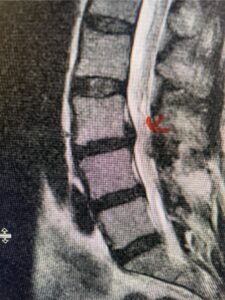

The next patient is a 56-year-old morbidly obese female who had progressive leg pain and weakness. She was over 320 lbs and did not have diabetes either. On MRI she had a massive disc herniation spanning the L3-4 and L-4 interspaces, centered behind the L4 vertebral body (Fig 3A and B). She also had an L4-5 spondylolisthesis. There were opinions that the disc emanated from the L3-4 disc space, but because of spondylolisthesis and on careful inspection of the MRI, there was a high chance the disc herniation had instead emanated from L4-5 (Fig 4). She had conservative treatment including epidurals but had worsening strength and numbness. She was scheduled electively for surgery, but then fell, and broke her ankle. She could not walk, particularly due to the pain down her leg. She was taken to the operating room urgently after she was cleared medically. She had no issues cardiologically and was taken to the operating room. The patient underwent a laminectomy that extended above the L3-4 disc space to below the L4-5 disc space. We encountered mainly centered on the left at the level of the L4 vertebral body and massive disc herniation that created a huge cavity in the lumbar canal. It was covered in an interesting thin membrane that we dissected off the disc herniation (Fig 5). Postoperatively the patient did experience significant relief of pain, but some improvement of strength. In combination with the ankle fracture and the extent of preoperative weakness, the patient required extensive rehab. The patient also developed a seroma and some wound drainage issues that were treated locally.

Fig 4: Sagittal T2-weighted lumbar MRI demonstrating an L4-5 grade 1 spondylolisthesis with obvious emanation of the disc herniation from the L4-5 level (red arrow)